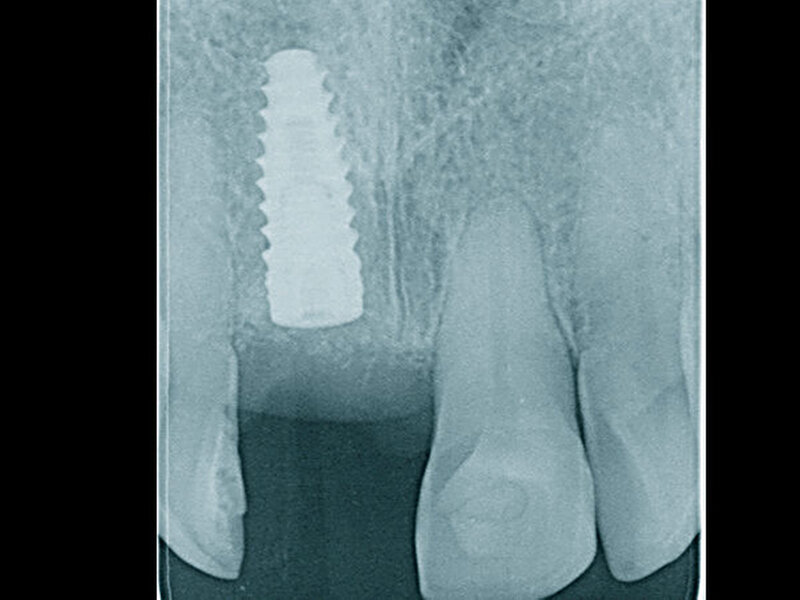

In welchen klinischen Anwendungen bietet das Implantat Vorteile?Hermann:Das neue CAMLOG PROGRESSIVE-LINE Implantat besticht durch sein innovatives parallel-konisches Makrodesign mit einem speziellen Gewinde, bei gleichzeitig bewährter Prothetikschnittstelle der Camlog-Linie. Dies bedeutet, dass in der chirurgischen Phase mit diesem Implantat eine zuverlässige Primärstabilität erzielt werden kann, speziell bei schwierigen anatomischen Voraussetzungen, wie z. B. bei der Sofortimplantation, bei reduzierter Kieferkammbreite oder konkav verlaufenden Alveoloarkämmen sowie bei weichem Knochen im Oberkiefer. Aufgrund des krestalen Verankerungsgewindes sehen wir zudem einen Vorteil bei der Platzierung des Implantats im Zusammenhang mit einer simultanen, offenen Sinusbodenelevation bei stark reduzierter Restknochenhöhe (2–3 mm). Auch einzeitige Verfahren lassen sich einfacher durchführen. Denn auch im kompromittierten Knochen erreicht das Implantat eine hohe vorhersagbare Primärstabilität.

Sind dann auch eher Sofortversorgungsprotkolle umzusetzen?Hermann:Die erzielte Primärstabilität ist in den meisten Fällen so hoch, dass eine sofortige provisorische Versorgung/Belastung möglich ist. Somit können wir unseren Patienten effiziente Behandlungsabläufe anbieten. Die Effizienz zeigt sich beispielsweise auch bei der Reduktion der Bohrschritte durch ein flexibles Bohrprotokoll. Gerade im weichen Knochen benötigen wir meist nur drei Bohrschritte bis zur Insertion des Implantats und erzielten eine exzellente Primärstabilität durch eine geringere Aufbereitung des Implantatbetts. Auf den zusätzlichen Einsatz nicht-ablativer Techniken (Osteotome) kann häufig verzichtet werden. Ein Teil der 80 von uns gesetzten PROGRES ‧ SIVE- ‧ LINE Implantate befindet sich bereits in der prothetischen Nachkontrolle. Das klinische und prothetische Outcome ist hervorragend. Es gibt weder chirurgische Komplikationen noch Probleme bei der Einheilung, und die prothetische Versorgung funktioniert perfekt.

Ihr Fazit? Hermann:Zusammenfassend kann ich sagen, dass wir mit der CAMLOG PROGRESSIVE-LINE eine Erweiterung der klinischen Indikationen in Bezug auf eine simultane Vorgehensweise (Implantation und Augmentation kombiniert) beobachtet haben, und zwar aufgrund der bereits erwähnten Primärstabilität bei schwierigen anatomischen Situationen. So können wir in vielen Fällen auch eine Sofortversorgung/Sofortbelastung des Implantats in Erwägung ziehen. Die situative Adaptation des Bohrprotokolls verschafft uns eine effiziente Insertion, die vorhandene, bewährte Prothetikschnittstelle der Implantate von CAMLOG das vertraute Handling, und dies alles bei einem Implantat, das wir bei allen klinischen Situationen zum Einsatz bringen konnten.